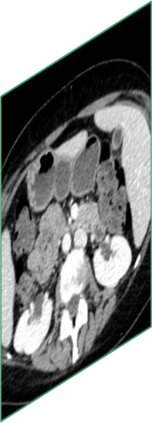

Due to the constraints of the imaging device and high cost in operation time, computer tomography (CT) scans are usually acquired with low intra-slice resolution. Improving the intra-slice resolution is beneficial to the disease diagnosis for both human experts and computer-aided systems. To this end, this paper builds a novel medical slice synthesis to increase the between-slice resolution. Considering that the ground-truth intermediate medical slices are always absent in clinical practice, we introduce the incremental cross-view mutual distillation strategy to accomplish this task in the self-supervised learning manner. Specifically, we model this problem from three different views: slice-wise interpolation from axial view and pixel-wise interpolation from coronal and sagittal views. Under this circumstance, the models learned from different views can distill valuable knowledge to guide the learning processes of each other. We can repeat this process to make the models synthesize intermediate slice data with increasing inter-slice resolution. To demonstrate the effectiveness of the proposed approach, we conduct comprehensive experiments on a large-scale CT dataset. Quantitative and qualitative comparison results show that our method outperforms state-of-the-art algorithms by clear margins.